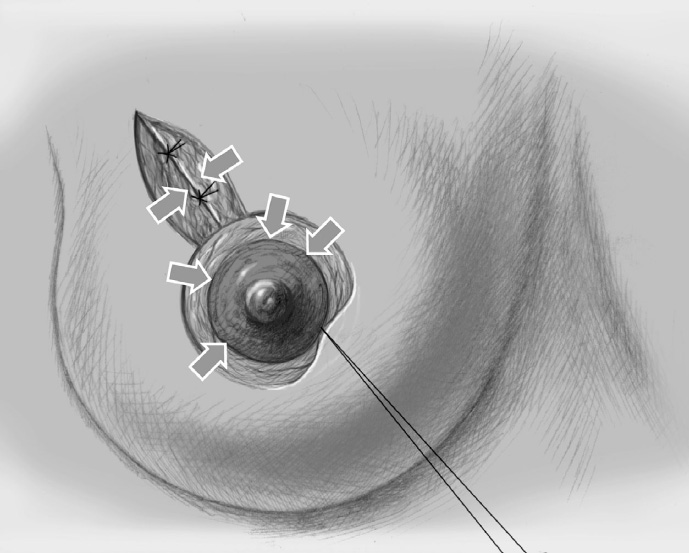

The basic decision on whether to use a complex oncoplastic technique is made when the skin is marked preoperatively, with the patient standing or sitting upright. Many surgeons successfully combine the B-plasty incision with periareolar de-epithelialization and excision of a straight or curved ellipse of peripheral skin (Chapter 1.3). When marking the periareolar deepithelialization pattern, an eccentric incision may be necessary to adjust the repositioning of the nipple–areola complex to the anticipated volume displacement.

The skin is incised superficially along the preoperative mark, initially with a scalpel. Many surgeons then proceed using electrocautery needle or scissors.

The periareolar skin is de-epithelialized. Here, too, there are various options. A strip of the most superficial skin layer can be excised with dissecting scissors applied flat or with a scalpel. It is important not to leave behind any surface containing squamous epithelium, but on the other hand the dermis and the important vascular layer beneath it must not be injured. The purpose of periareolar de-epithelialization is to recenter the nipple–areola complex and also to tailor excess skin to the new breast shape following extensive tumor resection.

Segmental excision of the area containing the tumor with resection margins as wide as possible to meet oncological criteria. Oncoplastic techniques should be used to achieve maximal oncological safety and avoid subsequent further resection.

The former tumor region is marked with clips.

To cover the defect, the glandular lobes are mobilized from the adjacent parenchyma after subcutaneous dissection. The principle of intramammary lobe creation is to mobilize large parts of the breast (> 25%) either relative to the skin or relative to the pectoralis muscle. This “liberation” of the breast from one of its two planes of fixation allows adequate dissection and rotation of sufficient breast tissue. The Y-flap and rotation flap shown in Chapter 3.2.1 are examples of intramammary dissection.

The mobilized breast lobes are rotated into the defect and approximated by interrupted sutures. Complete covering of the defect is desirable.

The skin is closed in two layers with recentering of the nipple–areola complex using interrupted sutures (Vicryl 3–0) according to the preoperative de-epithelialization pattern, which can be corrected at this time.